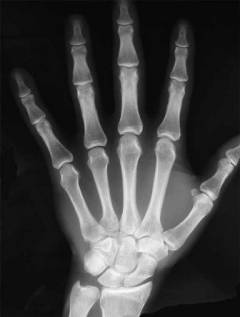

Запястье — часть верхней конечности между предплечьем и пястью. Основу составляют кости запястья и их соединения, расположенные в два ряда: проксимальном (ближе к предплечью) и дистальном (ближе к пясти). В каждом ряду по четыре кости. Дистальный ряд соединяется с пястными костями, проксимальный — с лучевой костью.

Костная структура запястья включает:

- ладьевидную кость;

- полулунную кость;

- трехгранную кость;

- гороховидную кость;

- многоугольную кость;

- трапециевидную кость;

- головчатую кость;

- крючковидную кость.

Суставы запястья малоподвижны, так как укреплены связками и сухожилиями.